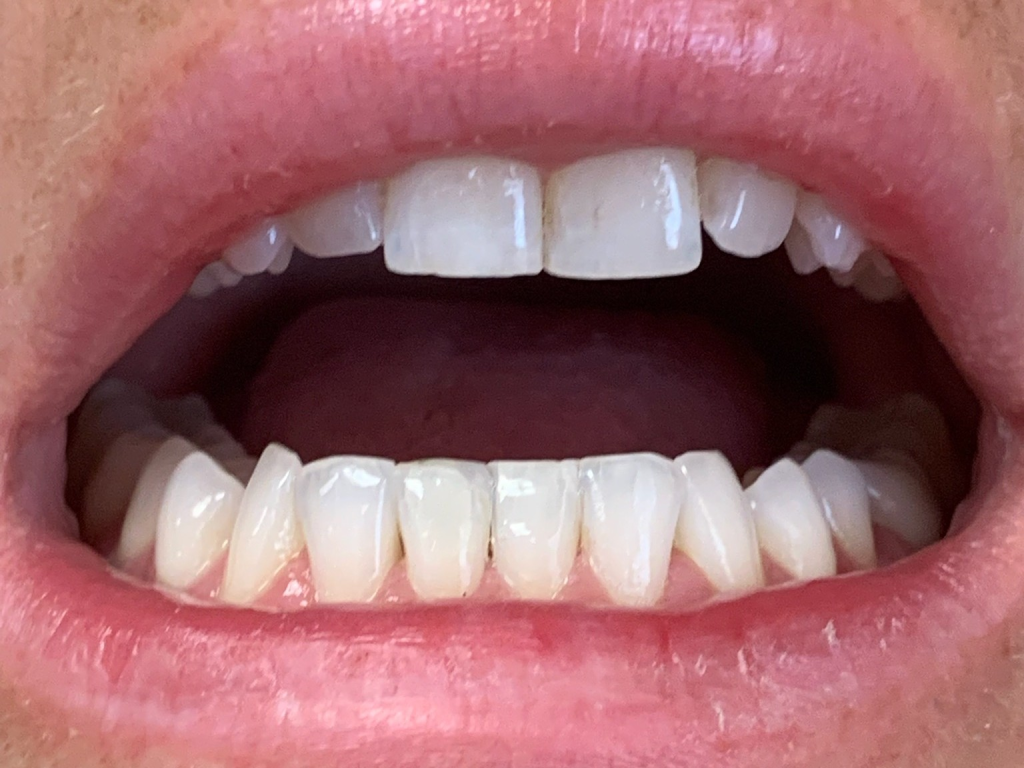

Anterior broken tooth. Double DentXpinTM repair.

3